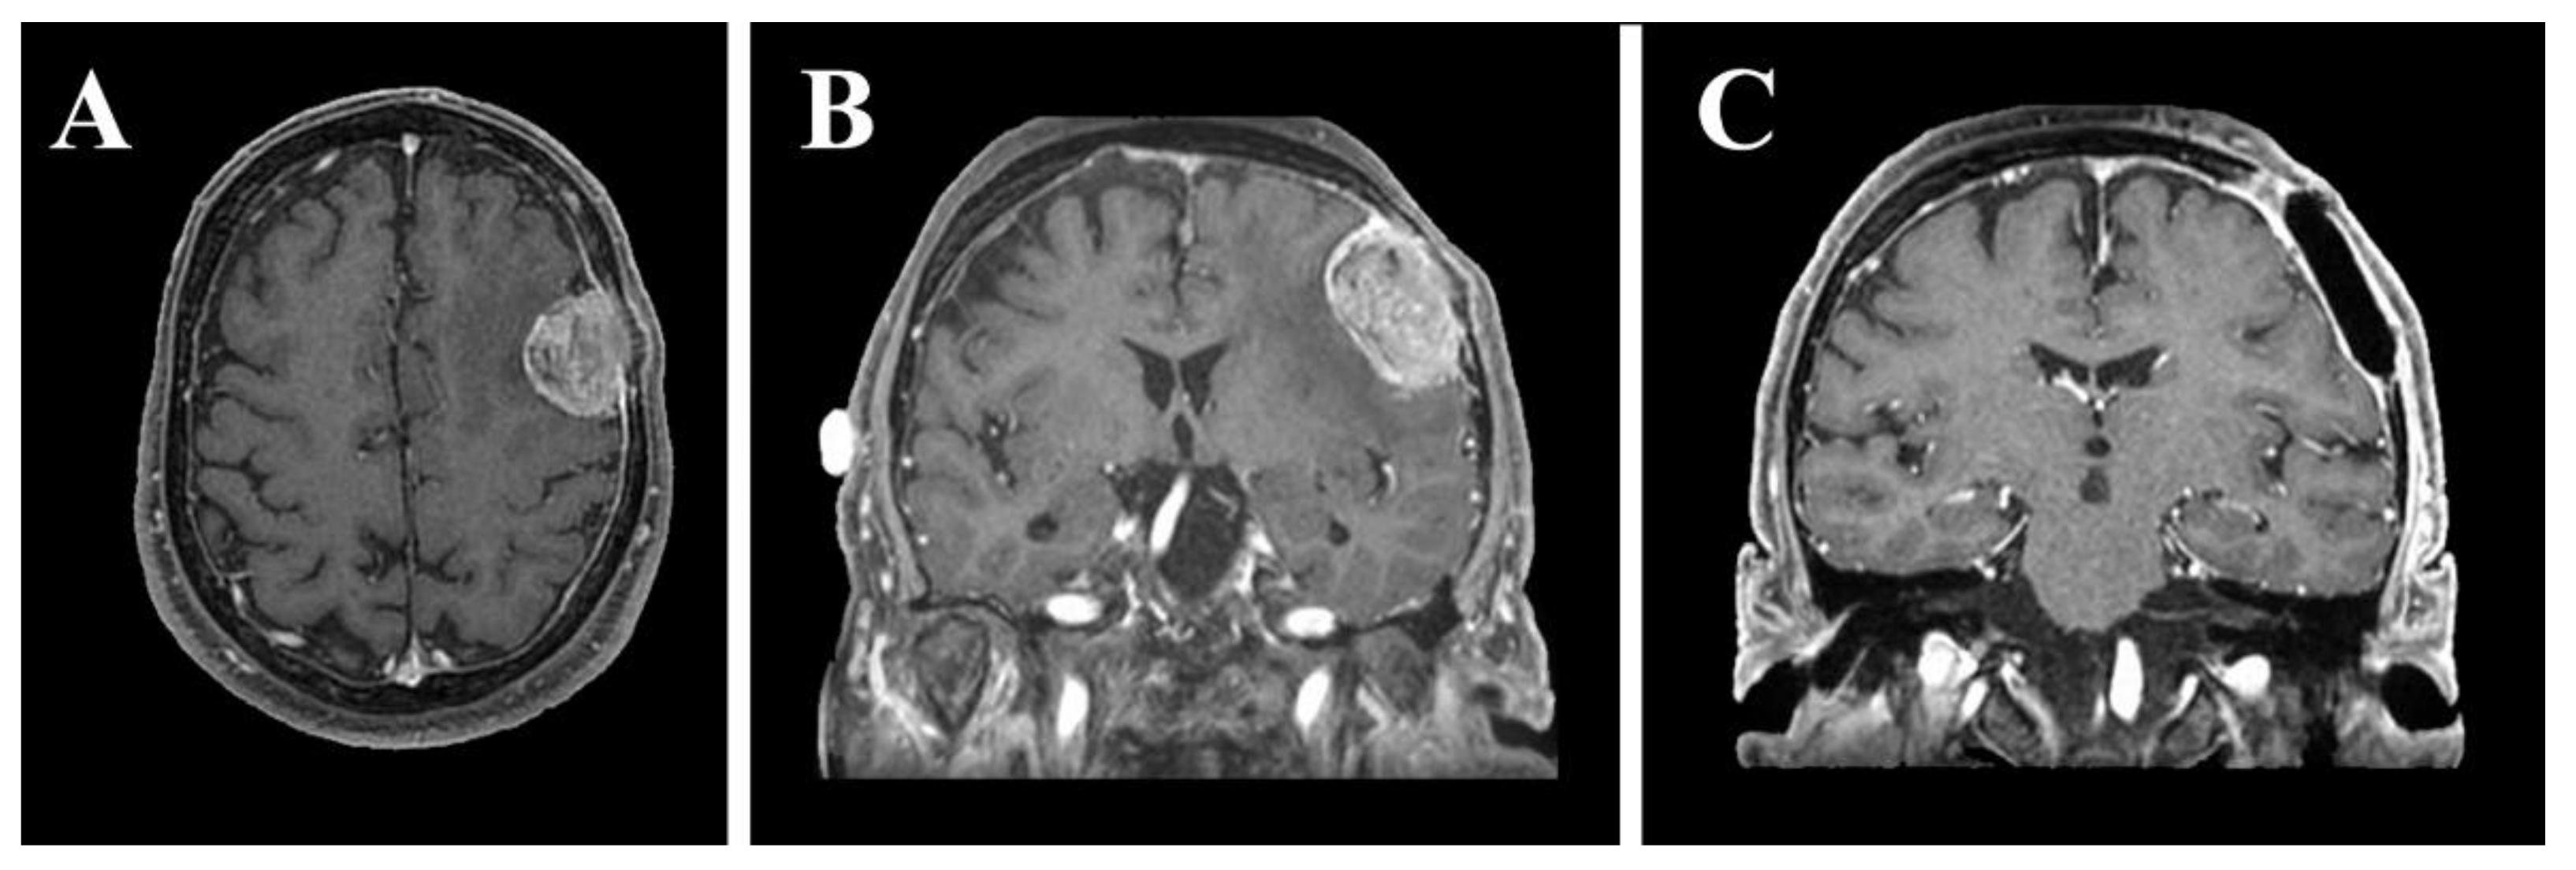

2. Materials and Methods

2.2. VOSTARS HMD-Based Surgical Navigation Platform and Template-Based Registration

3. Results